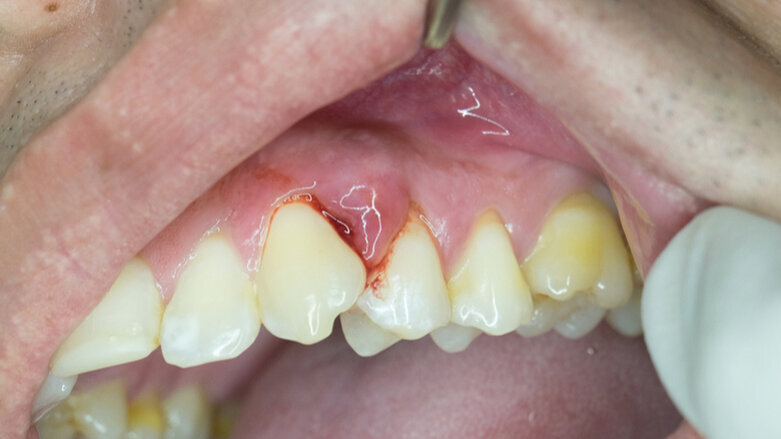

Laut Studien haben Diabetiker ein dreifach erhöhtes Risiko an Parodontitis zu erkranken. © trailak amtim/Shutterstock

Laut Studien haben Diabetiker ein dreifach erhöhtes Risiko an Parodontitis zu erkranken. Sie weisen zudem eine beschleunigte Progression parodontaler Erkrankungen und eine reduzierte Therapieantwort auf eine Parodontitisbehandlung auf. Das zunehmende Parodontitisrisiko ist vor allem mit ungenügend eingestelltem Diabetes verbunden.